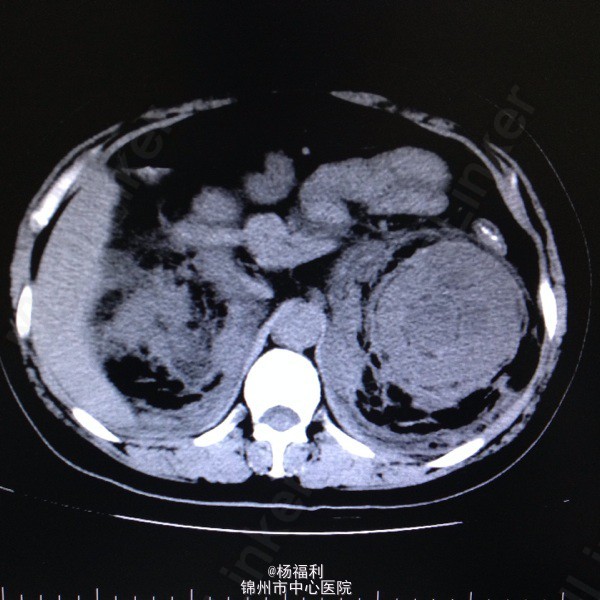

44岁女患。为消化科我会诊患者。 现病史:以上腹痛9小时为主诉入院。无发热及寒战、噁心未呕吐,无腹泻及黑便。 既往史:双眶炎性假瘤2年,口服激素治疗,并补钾。

查体:上腹部压痛,无反跳痛、右侧压痛明显,右肾区叩击痛,左肾区轻叩击痛,双输尿管走形区无压痛。 辅助检查;泌尿系彩超:双肾积水。 血白细胞:9.99*10^9。 肾功能正常。 全腹部ct及MRU检查:见图片。

诊断;真的不知道是啥病。 处理:暂时止痛处理。双肾病变。不知从哪里下手。